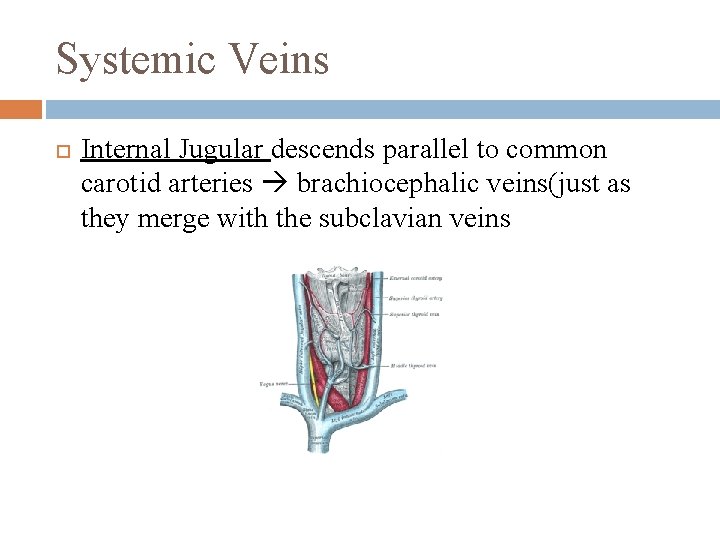

Systemic Veins Internal Jugular descends parallel to common carotid arteries brachiocephalic veins(just as they merge with the subclavian veins